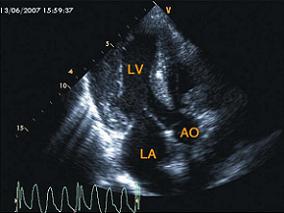

1小时条评论【病例3】 病例和相关检查 患者,男性,56岁,6个月前无明显诱因出现乏力,活动后气短,腹泻,消瘦,近3个月来双下肢水肿。查体:双下肢水肿,心脏听诊心律齐,未闻及明显杂音。 超声图片 如图2‐1‐213,图2‐1‐214。 图2‐1‐213 心尖左室长轴切面前室间隔及...